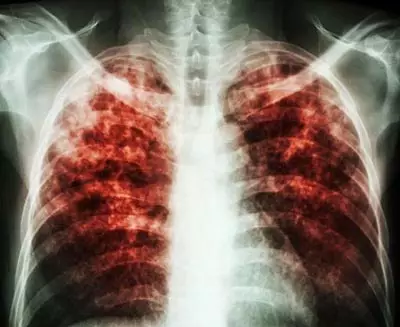

慢阻肺肺氣腫總是治不好?你可能踩到了這三大雷區(qū)!

慢阻肺跟高血壓一樣也是一種慢性病,早期治療事半功倍,長(zhǎng)期而有計(jì)劃的綜合治療是治療疾病的關(guān)鍵所在。

其實(shí),慢阻肺跟高血壓一樣也是一種慢性病,早期治療事半功倍,長(zhǎng)期而有計(jì)劃的綜合治療是治療疾病的關(guān)鍵所在。

慢阻肺屬于冬病,冬天容易發(fā)作。而現(xiàn)在是夏天,多數(shù)患者的病情處于穩(wěn)定期,各種癥狀都比較輕。大部分慢阻肺患者卻忽略了治療,錯(cuò)失了良機(jī)。有種說(shuō)法是“急性加重期是救命的,穩(wěn)定期才是治病的”,因此提倡大家冬病夏治。

慢阻肺肺氣腫是慢性病,需要慢慢治療?;颊邞?yīng)該有計(jì)劃地綜合性的長(zhǎng)期治療,以達(dá)到防微杜漸的作用,減緩疾病發(fā)展的速度,減少急性發(fā)作和并發(fā)癥的發(fā)生。

所以,治療肺氣腫、慢阻肺這些慢性病,切莫錯(cuò)失良機(jī),不可急于求成,更不能見好就收。關(guān)鍵在于長(zhǎng)期堅(jiān)持疏通氣道、排出黏痰、排出二氧化碳,輕輕松松就能在家治療,減少發(fā)病,減少住院。